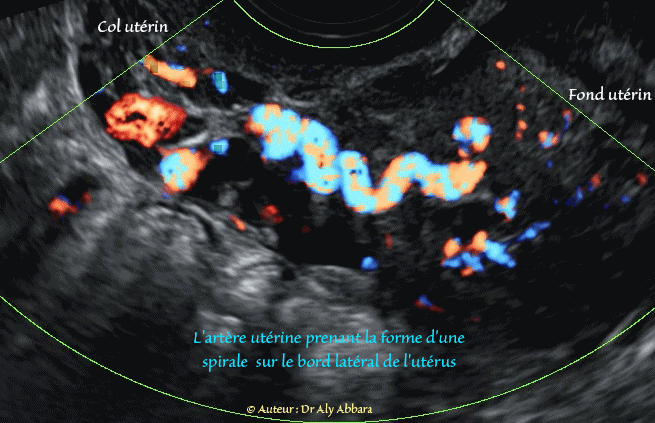

La portion terminale de l'artère utérine prenant la forme d'une spirale sur le bord latéral de l'utérus (ici : côté gauche) 1

La portion terminale de l'artère utérine prenant la forme d'une spirale sur le bord latéral de l'utérus (ici : côté gauche)

Utérus non gravide

Auteur : Dr Aly Abbara